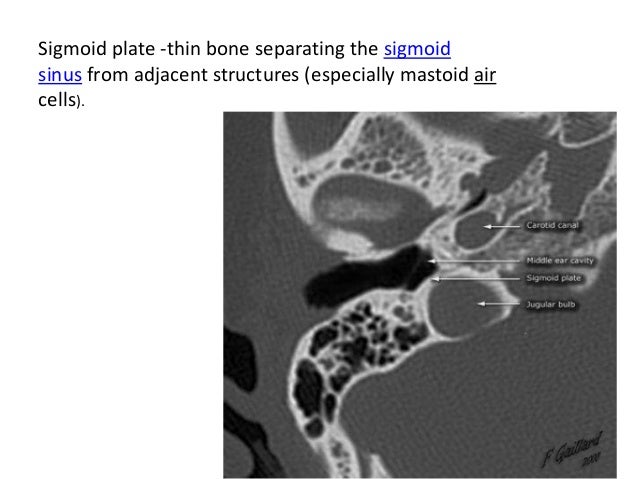

Ct Scan Temporal Bone Dr Zeeshan Ahmad

Ct scan temporal bone Dr Zeeshan Ahmad www.slideshare.net

zeeshan aqueduct

Zeeshan aqueduct. Temporal bone skull base fig. Ch07 a.skeletal